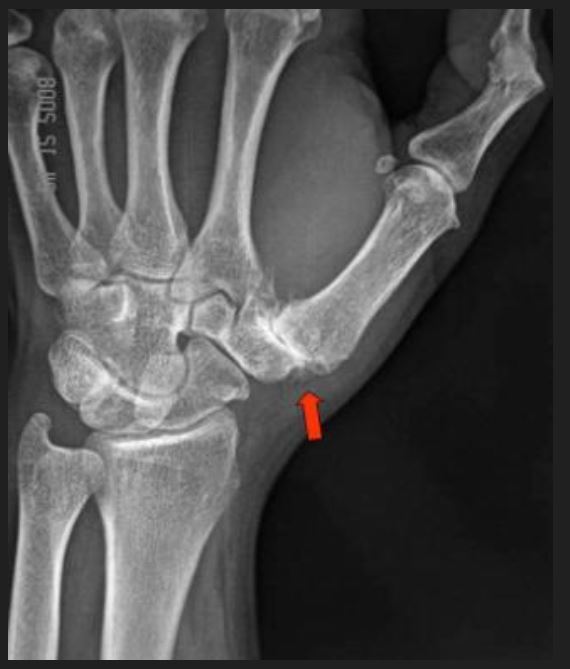

Basilar thumb OA:

1. Describe this radiograph.

This is a plain radiograph of the left hand in AP projection.

with joint space narrowing at the 1st CMCJ with sclerosis and osteophytes > 2mm. Mention also no STT arthritis noted (means not end stage).

**Plain radiograph i will order is AP, Lat and Robert’s view of the thumb.

• *2. What is your diagnosis? What are your differential diagnosis?**

• Basilar thumb arthritis = 1st carpo-metacarpal joint arthritis.

Eaton and Littler Classification of Basilar Thumb Arthritis

Stage I to IV: based on degree of degeneration and subluxation of the joint

Stage I- Slight joint space widening (pre-arthritis)

Stage II- Slight narrowing of CMC joint with sclerosis, osteophytes <2mm

Stage III- Marked narrowing of CMC joint with sclerosis, osteophytes >2mm

Stage IV-Pantrapezial arthritis (STT-ScaphoidTrapeziumTrapezoid involved)

** In this case, patient is Stage III